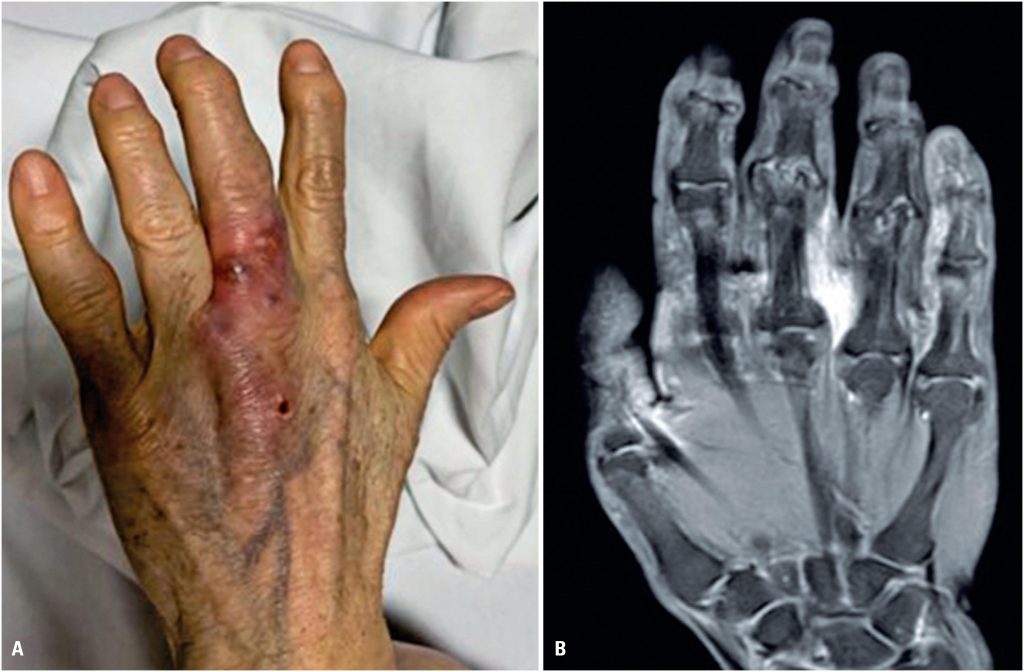

Fungal infections have become a public health problem owingdute to their progressive increase in recent decades and high morbidity rates. Fungal bone and joint infections result from direct inoculation, contiguous infection spread, or hematogenous seeding of organisms. Trichosporon spp. are yeast-like basidiomycetes, with Trichosporon asahii being the most common pathogenic species. This article describes a rare case of tenosynovitis caused by Trichosporon asahii in an immunocompetent patient. Treatment with voriconazole resulted in an excellent clinical response.